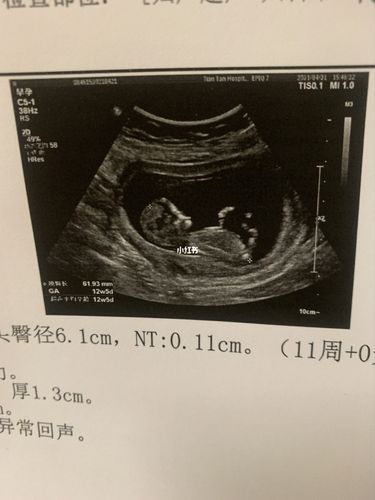

男女nt图对比,女宝nt图片

nt归来,有会看男女的亲吗?

nt过了,能看男女吗

nt nub点看男女_nt检查_女宝_母婴_孕产经验

附一张nt数据有会看男女的嘛头胎男女

女宝nt图片

生男宝的NT图片

已生女宝nt图

已生男宝nt图

男宝nt图片

nt图

nt值看男女

nt男女图对照表

nt图看男女

nt看男女

NT图如何看男女